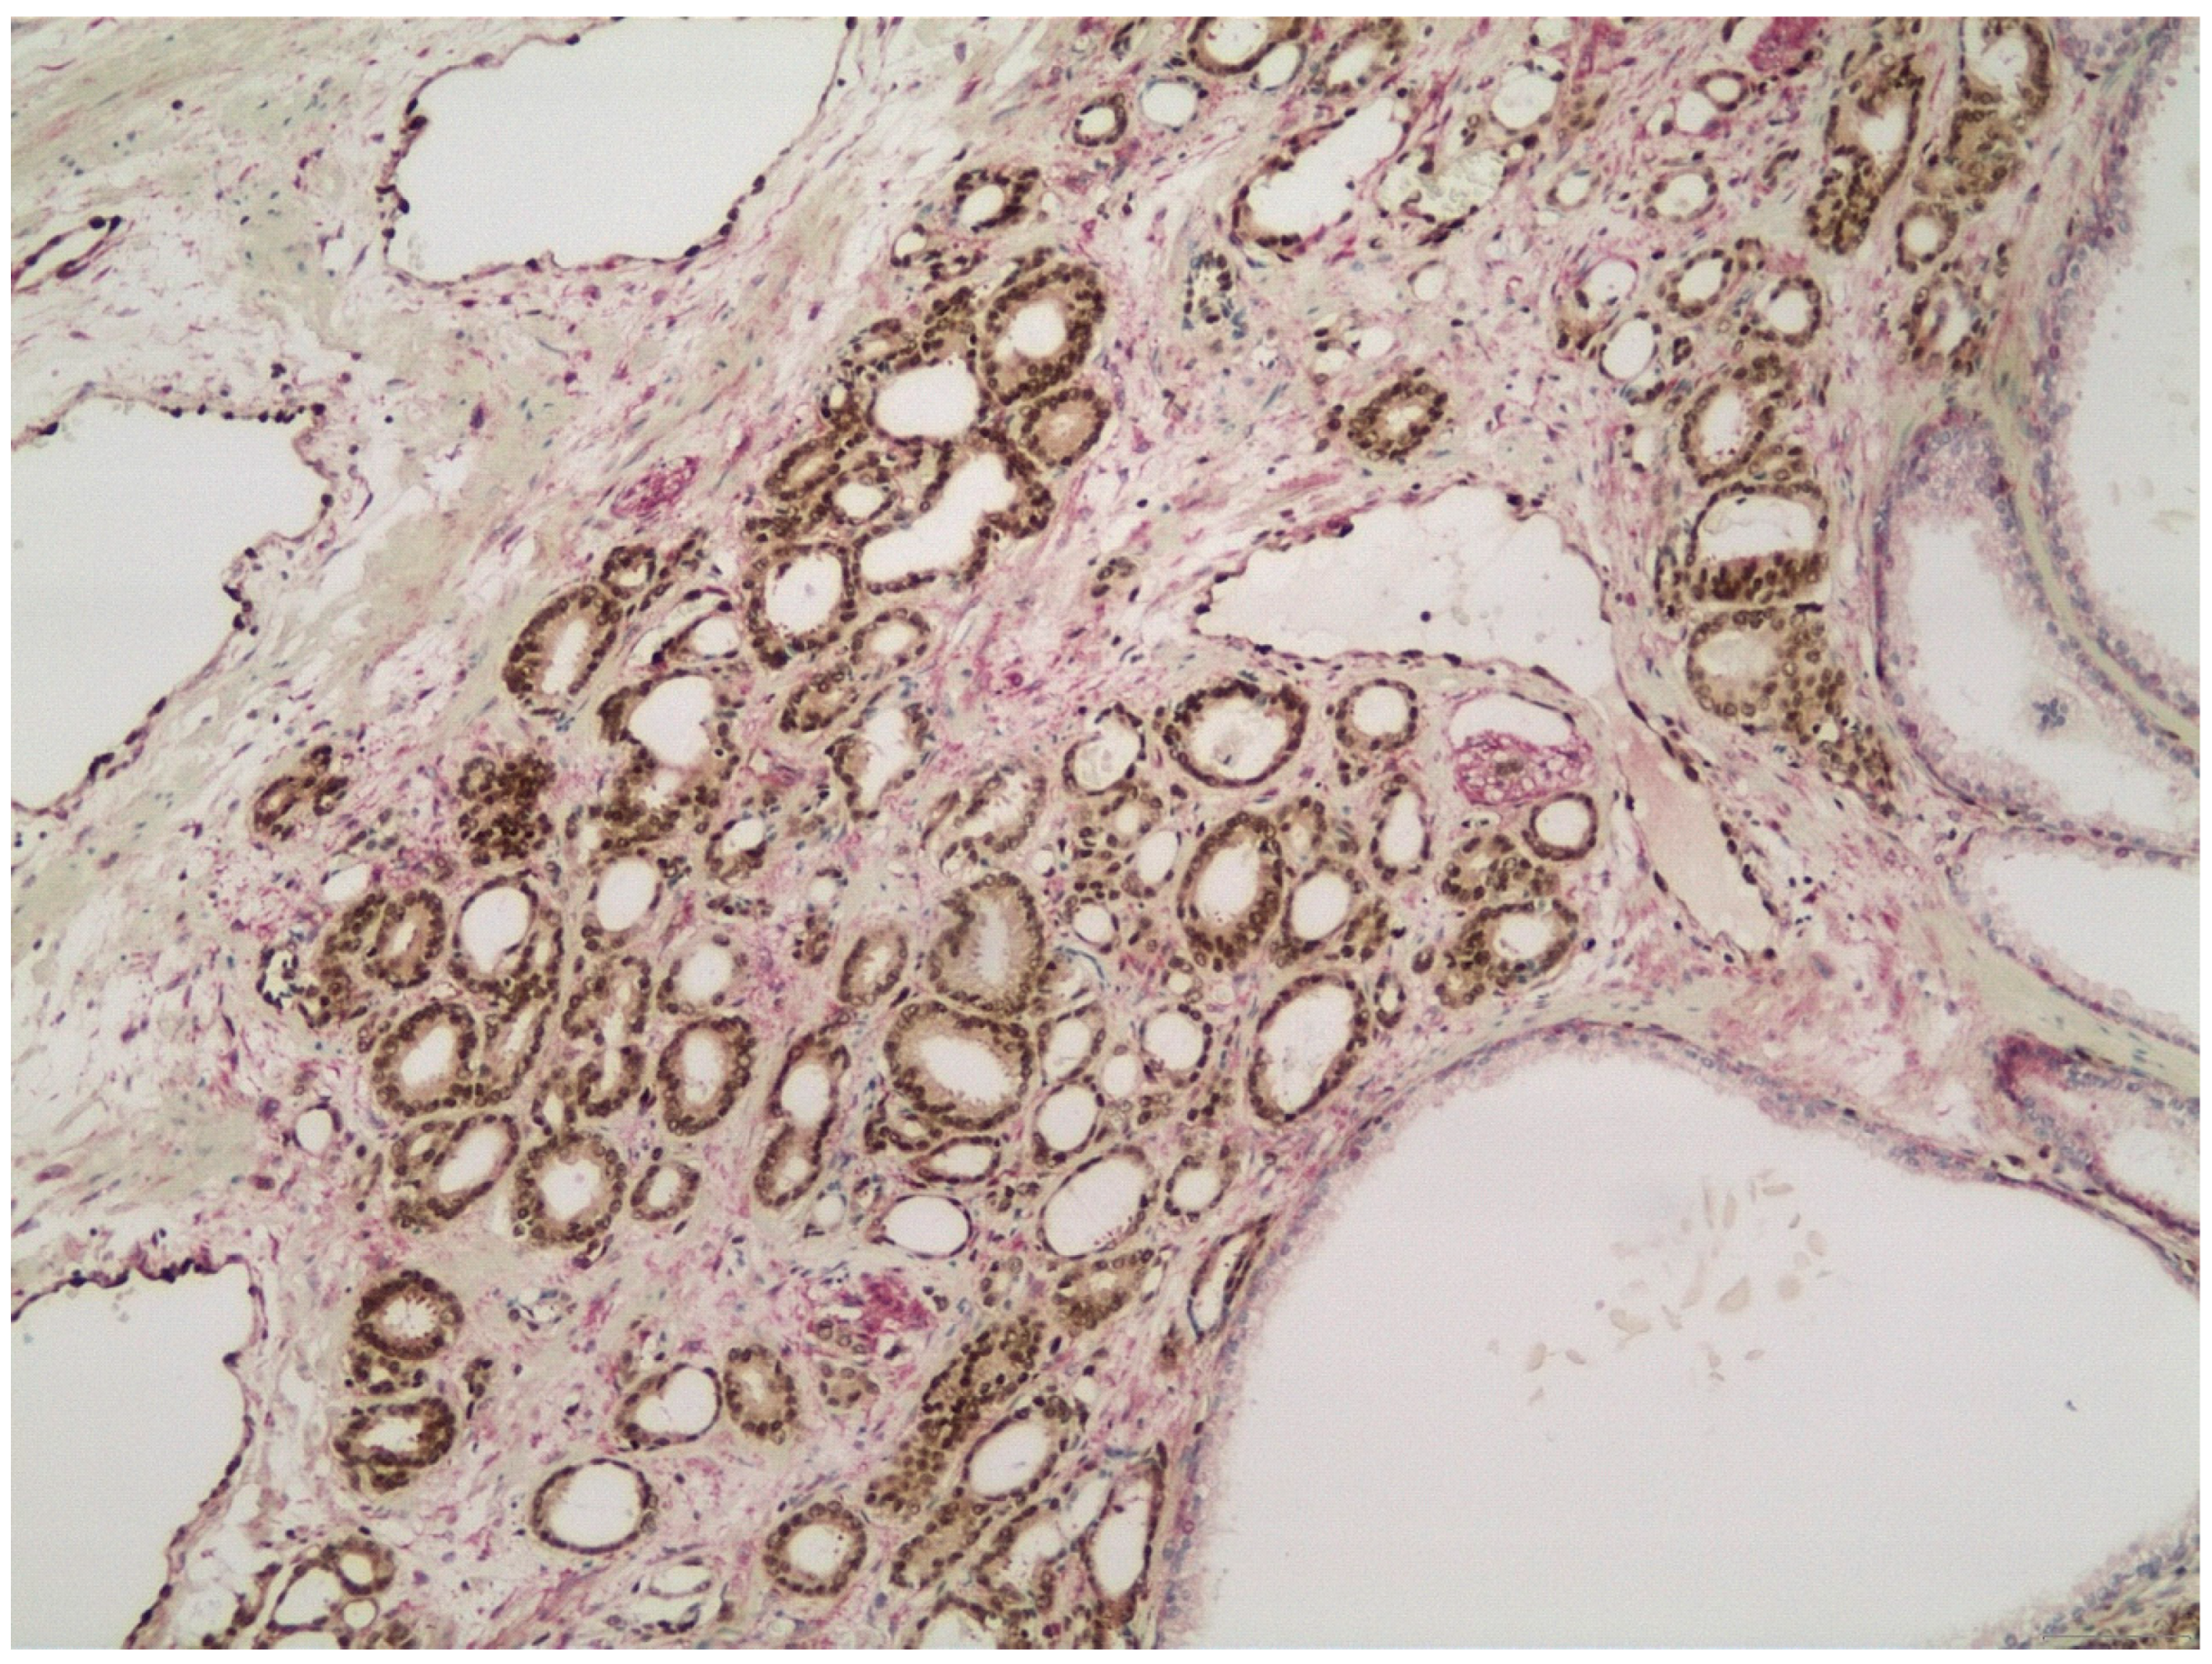

3.3. PTEN Expression in HGPIN and Its Association with the Adjacent Invasive Prostate Cancer

3.4. ERG Expression in IDCP and Its Association with the Adjacent Invasive Prostate Carcinoma